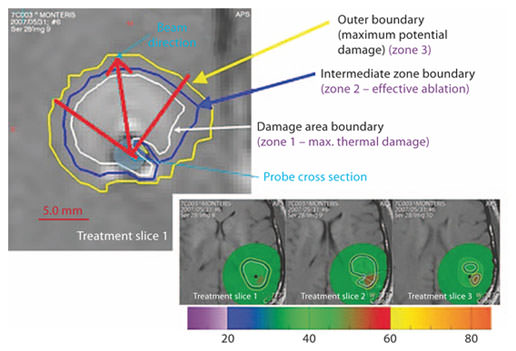

For the procedure we used the AutoLITT® (Monteris Medical Inc., Winnipeg, Canada) system which has received FDA 510(k) clearance for clinical use in the United States since 2009 without specific limitation for intracranial use. The device consists of: (a) a fiber-optic laser probe, (b) patient-probe interface, (c) probe driver, and (d) MR trajectory planning and thermometry workstation. This integrates with non-Monteris devices including a head-fixation device, 1.5 Tesla (T) intraoperative MRI scanner, and a Dornier diode laser (1,064 nm), CO2-cooled, focused, pulse-sequence diode laser which emits a beam 90° orthogonal to the probe. The novel technologies in this device allow the laser probe to focus energy in one specific direction (perpendicular to its tip) rather than in the omnidirectional pattern of previously used bare fiber-optic laser probes. In addition, gaseous cooling is used to prevent heat dissipation to adjacent, nontargeted areas. The combination of focused energy delivery and gaseous cooling of the tip allows for conformal treatments. The probe, laser, and cooling are remotely controlled using real-time MR imaging and thermometry software.

Based on the temperatures reached within the lesion, three zones have been defined which can be visualized on the Monteris workstation while performing the procedure. Zone 1 is the region where maximal thermal damage has occurred, zone 2 is the outer limit of effective ablation, and zone 3 is where thermal changes occur without ablative effect (fig. 3). The goal of the procedure is to encompass the entire lesion within ablation zone 2 in order to be effective.

Zones of thermal lesioning: zone 1 (damage area boundary) within the white line being the region of maximal thermal damage, zone 2 (intermediate zone boundary) within the blue line indicating an effective ablation, and zone 3 (outer boundary) within the yellow line indicating temperature changes without any ablative effect. This figure is only representative of the various zones of thermal ablation.

Zones of thermal lesioning: zone 1 (damage area boundary) within the white line being the region of maximal thermal damage, zone 2 (intermediate zone boundary) within the blue line indicating an effective ablation, and zone 3 (outer boundary) within the yellow line indicating temperature changes without any ablative effect. This figure is only representative of the various zones of thermal ablation.